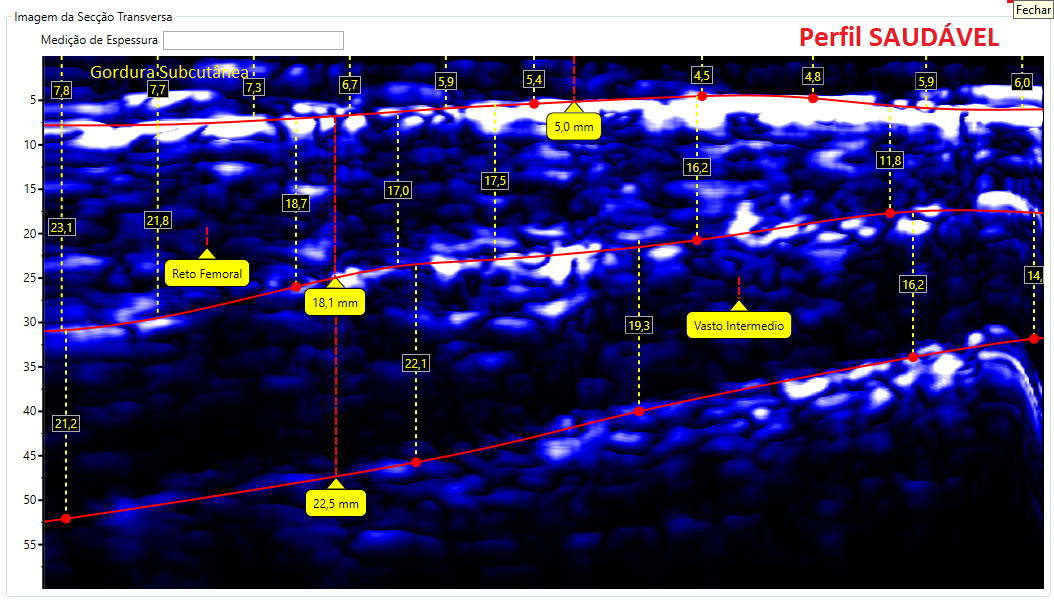

Comparativos de imagens de Coxa